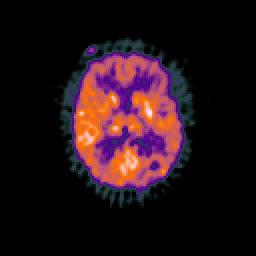

Glioma overlay -- Slice #63

[Home][Help][Clinical] Slice 63